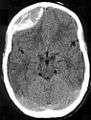

| Epidural hematoma. Note the biconvex shape hemorrhage. | |

On images produced by CT scans and MRIs, epidural hematomas usually appear convex in shape because their expansion stops at the skull's sutures, where the dura mater is tightly attached to the skull. Thus they expand inward toward the brain rather than along the inside of the skull, as occurs in subdural hematoma. The lens-like shape of the hematoma causes the appearance of these bleeds to be "lentiform."